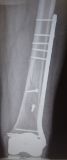

5. Periprosthetic fracture of the left femur in a 75-year-old male with a total knee arthroplasty.

Treatment: Open reduction internal fixation

I. Anteroposterior x-ray of the femur shows the periprosthetic fracture II. Post-surgery, x-ray shows the metal work and the reduction of the fracture. The arthroplasty was stable therefore there was no need in this stage for the replacement of the prothesis